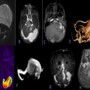

Legends

•A)Coronal T2W shows massively dilated proximal left transverse sinus possibly involving Torcula, suggestive of dural sinus malformation.

•B)Axial T1 PC shows contrast enhancement of the dural sinus malformation. No evidence of thrombosis within.

•C)Axial TOF MIP shows the fistula site to be located along the anterior, inferior and lateral aspects of the sac with prominent feeders from left internal carotid artery.

•D)Sagittal Volume rendered images show prominent arterial feeders from left middle meningeal artery and left occipital artery.

•E) Axial ASL sequence shows increased perfusion(arterial flow),suggestive of arteriovenous fistula.

•F) Coronal MRV MIP shows this dilated sac terminating as a prominent left sigmoid sinus with its continuity with the left internal jugular vein not being visualized, due to chronic occlusion.

•G) Axial T1 PC shows pprominent posterior fossa veins.

•H) Axial TOF MIP shows prominent bilateral superficial and deeper middle cerebral veins (right more than left) as well as dilated superior ophthalmic veins (right more than left) further draining across the canthi into supratrochlear veins been much more prominent in the right medial canthus. Also the dilated right superior ophthalmic vein is seen causing relative mass effect in the form of proptosis of the right eyeball.